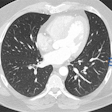

3D volumetry shows promise in lung but requires care